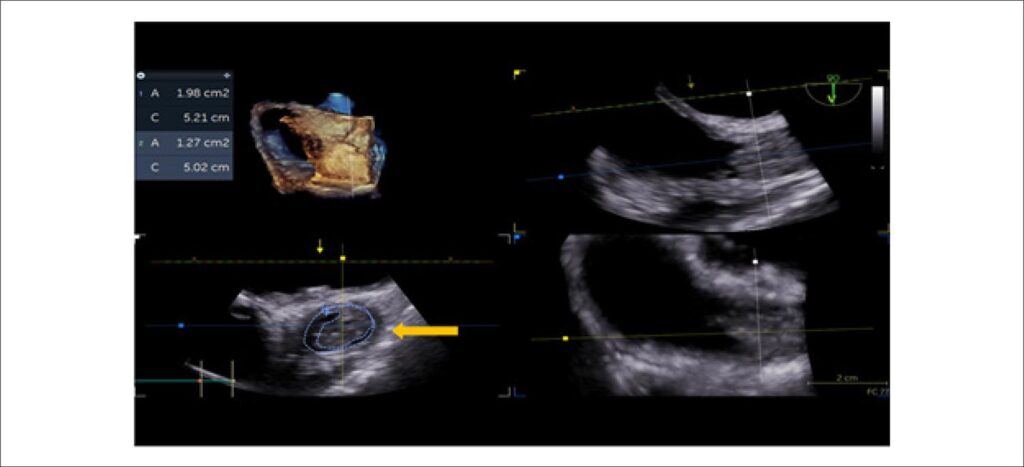

Transesophageal Echocardiogram in the Diagnosis of Superior Vena Cava Syndrome in a Patient With a Long-Term Catheter

The superior vena cava syndrome (SVCS) is caused by the obstruction or severe occlusion of the superior vena cava (SVC) and can result in significant morbidity or mortality., Malignancy is the most common cause of this obstruction, corresponding to approximately 70% of the cases. However, more recently, the incidence of SVCS related to devices, such as central venous catheters and electrodes of a pacemaker or defibrillator, have increased.,

These devices, together with states of hypercoagulability, can precipitate the formation of thrombi. In extreme situations, in the context of bacteremia, these can lead to the formation of a complex thrombus-vegetation association.